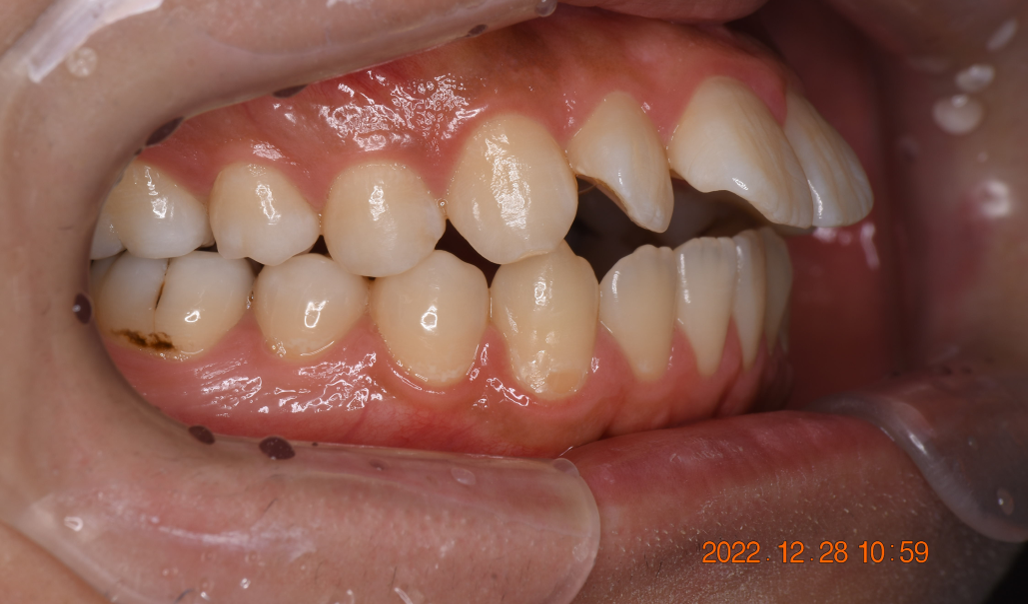

マウスピース型矯正装置(インビザライン)の症例

マウスピース型矯正装置(インビザライン)を使用した歯列矯正